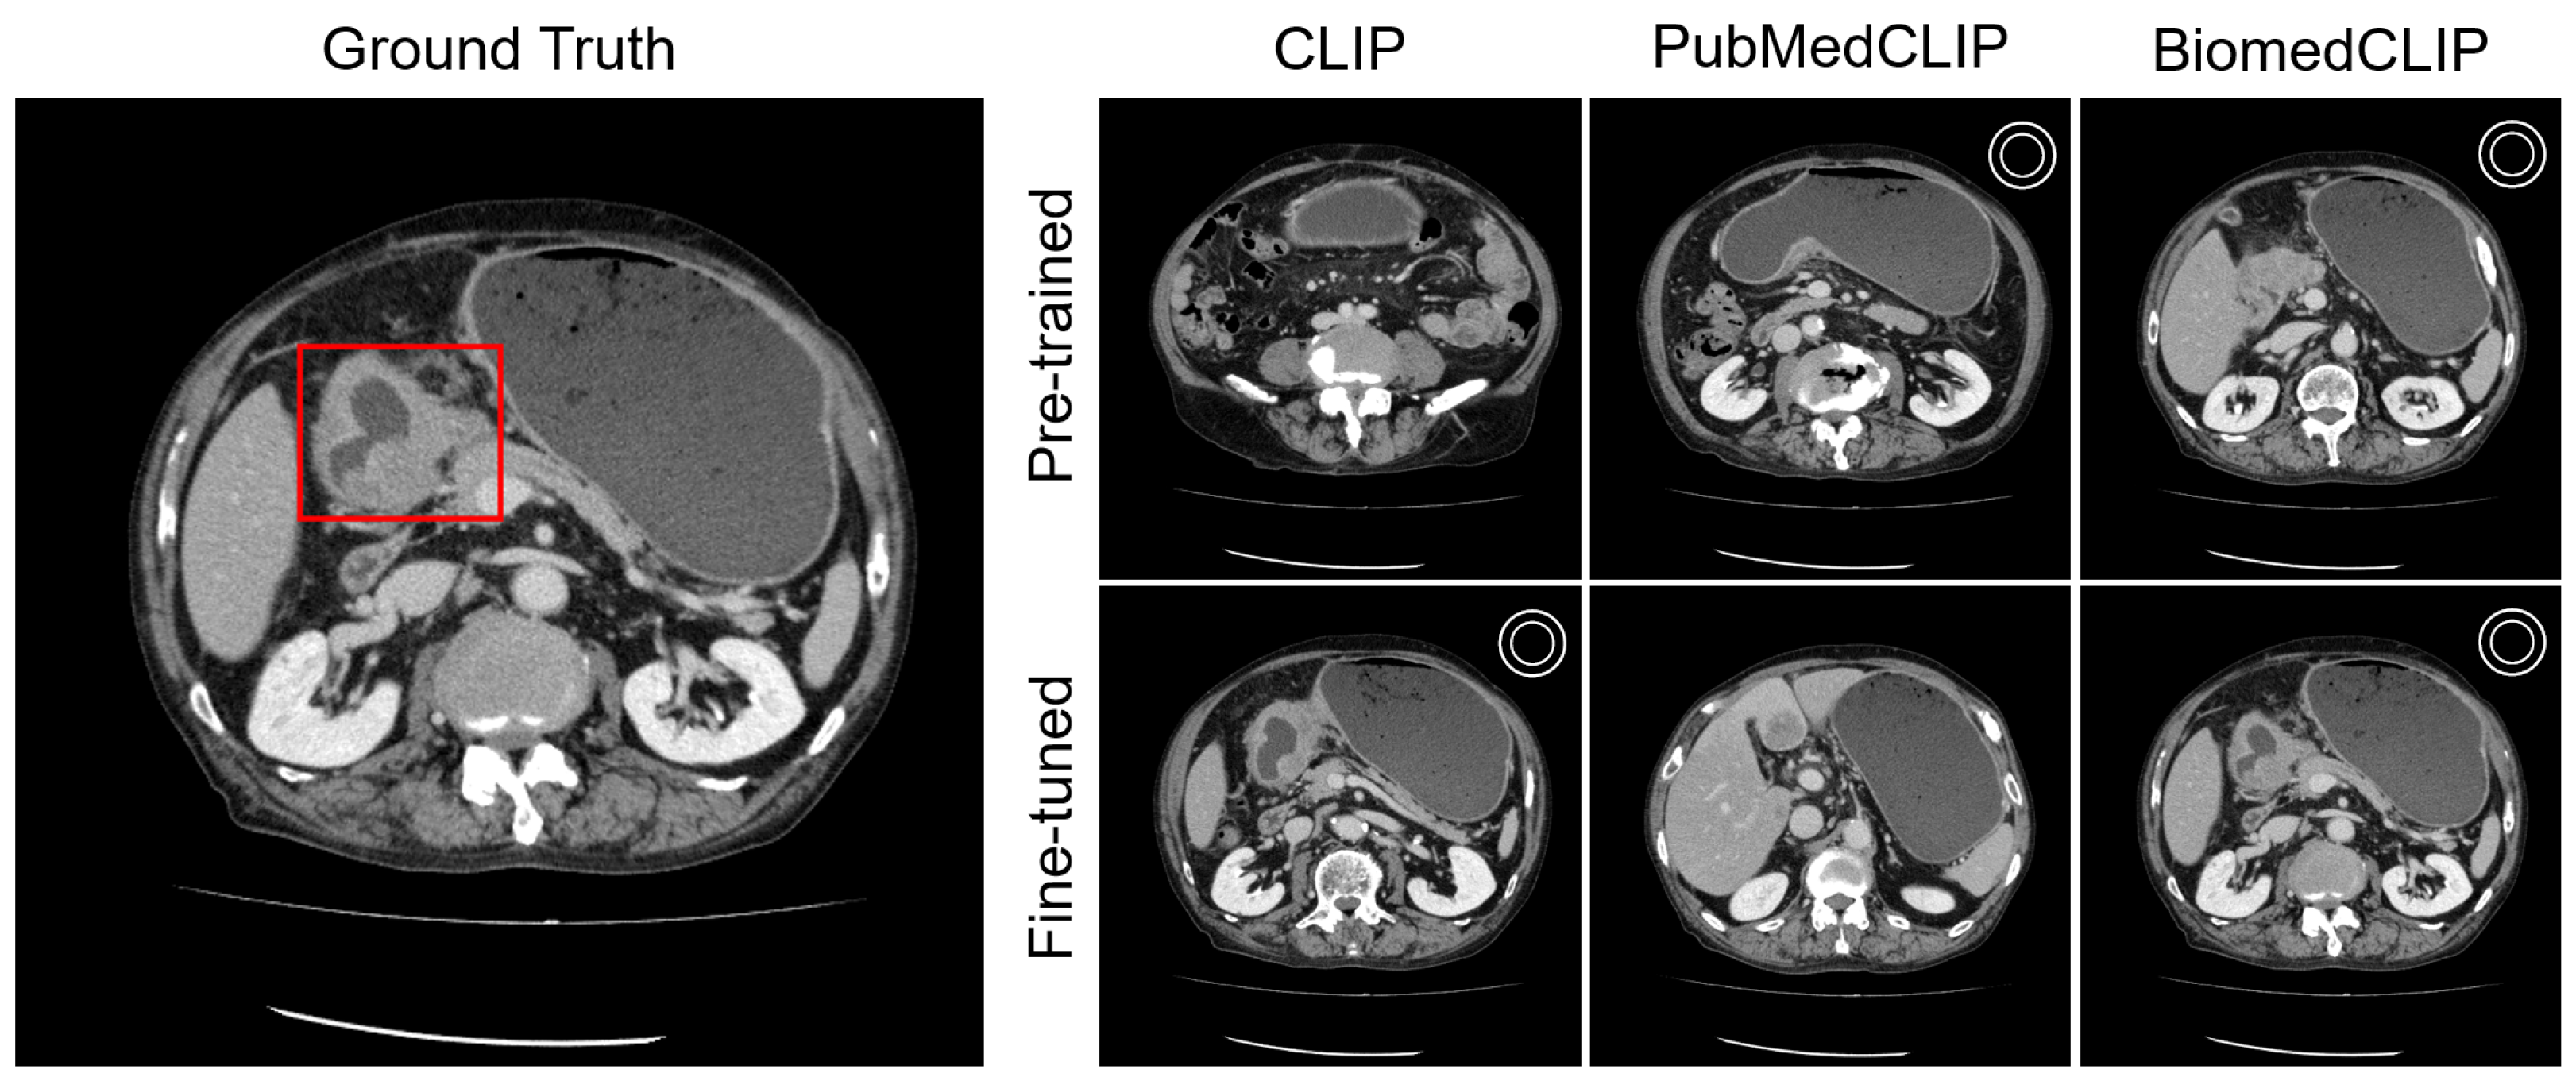

Appendix C.2. Organ Awareness